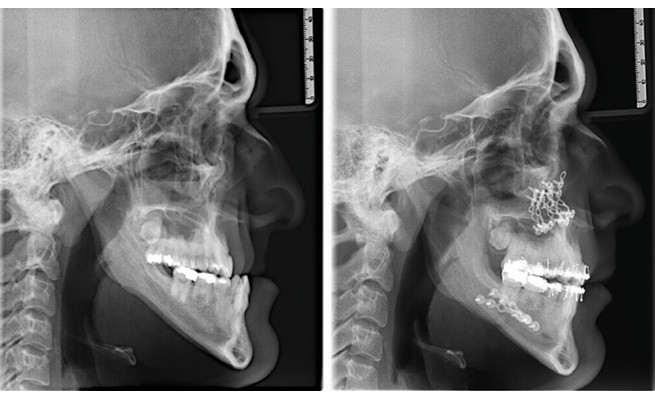

Fig. 1 : Après une chirurgie orthognatique, il y a une phase d’adaptation neuromusculaire qui peut durer plusieurs mois, durant laquelle le risque de décompensation fonctionnelle est maximal.